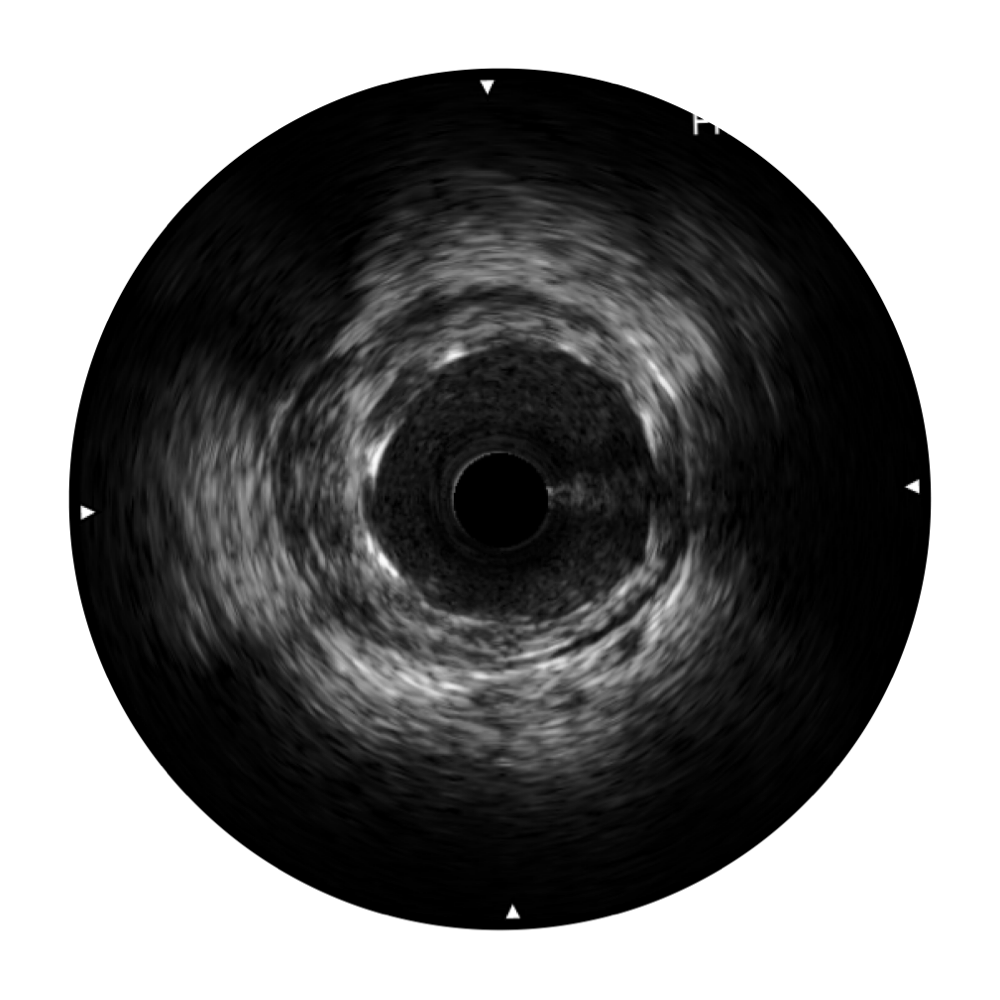

竞技宝(JJB)官方网站宽频IVUS图像

传统IVUS图像

对比传统IVUS导管成像,竞技宝(JJB)官方网站宽频IVUS图像的近场支架梁显影更细腻,远场中膜外血管仍清晰可辨,兼顾远中近,兼顾分辨力与穿透深度